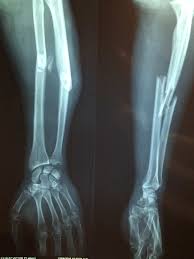

Bone Fractures & Sprains

كسور العظام وا لالتواءات (Bone Fractures and Sprains)